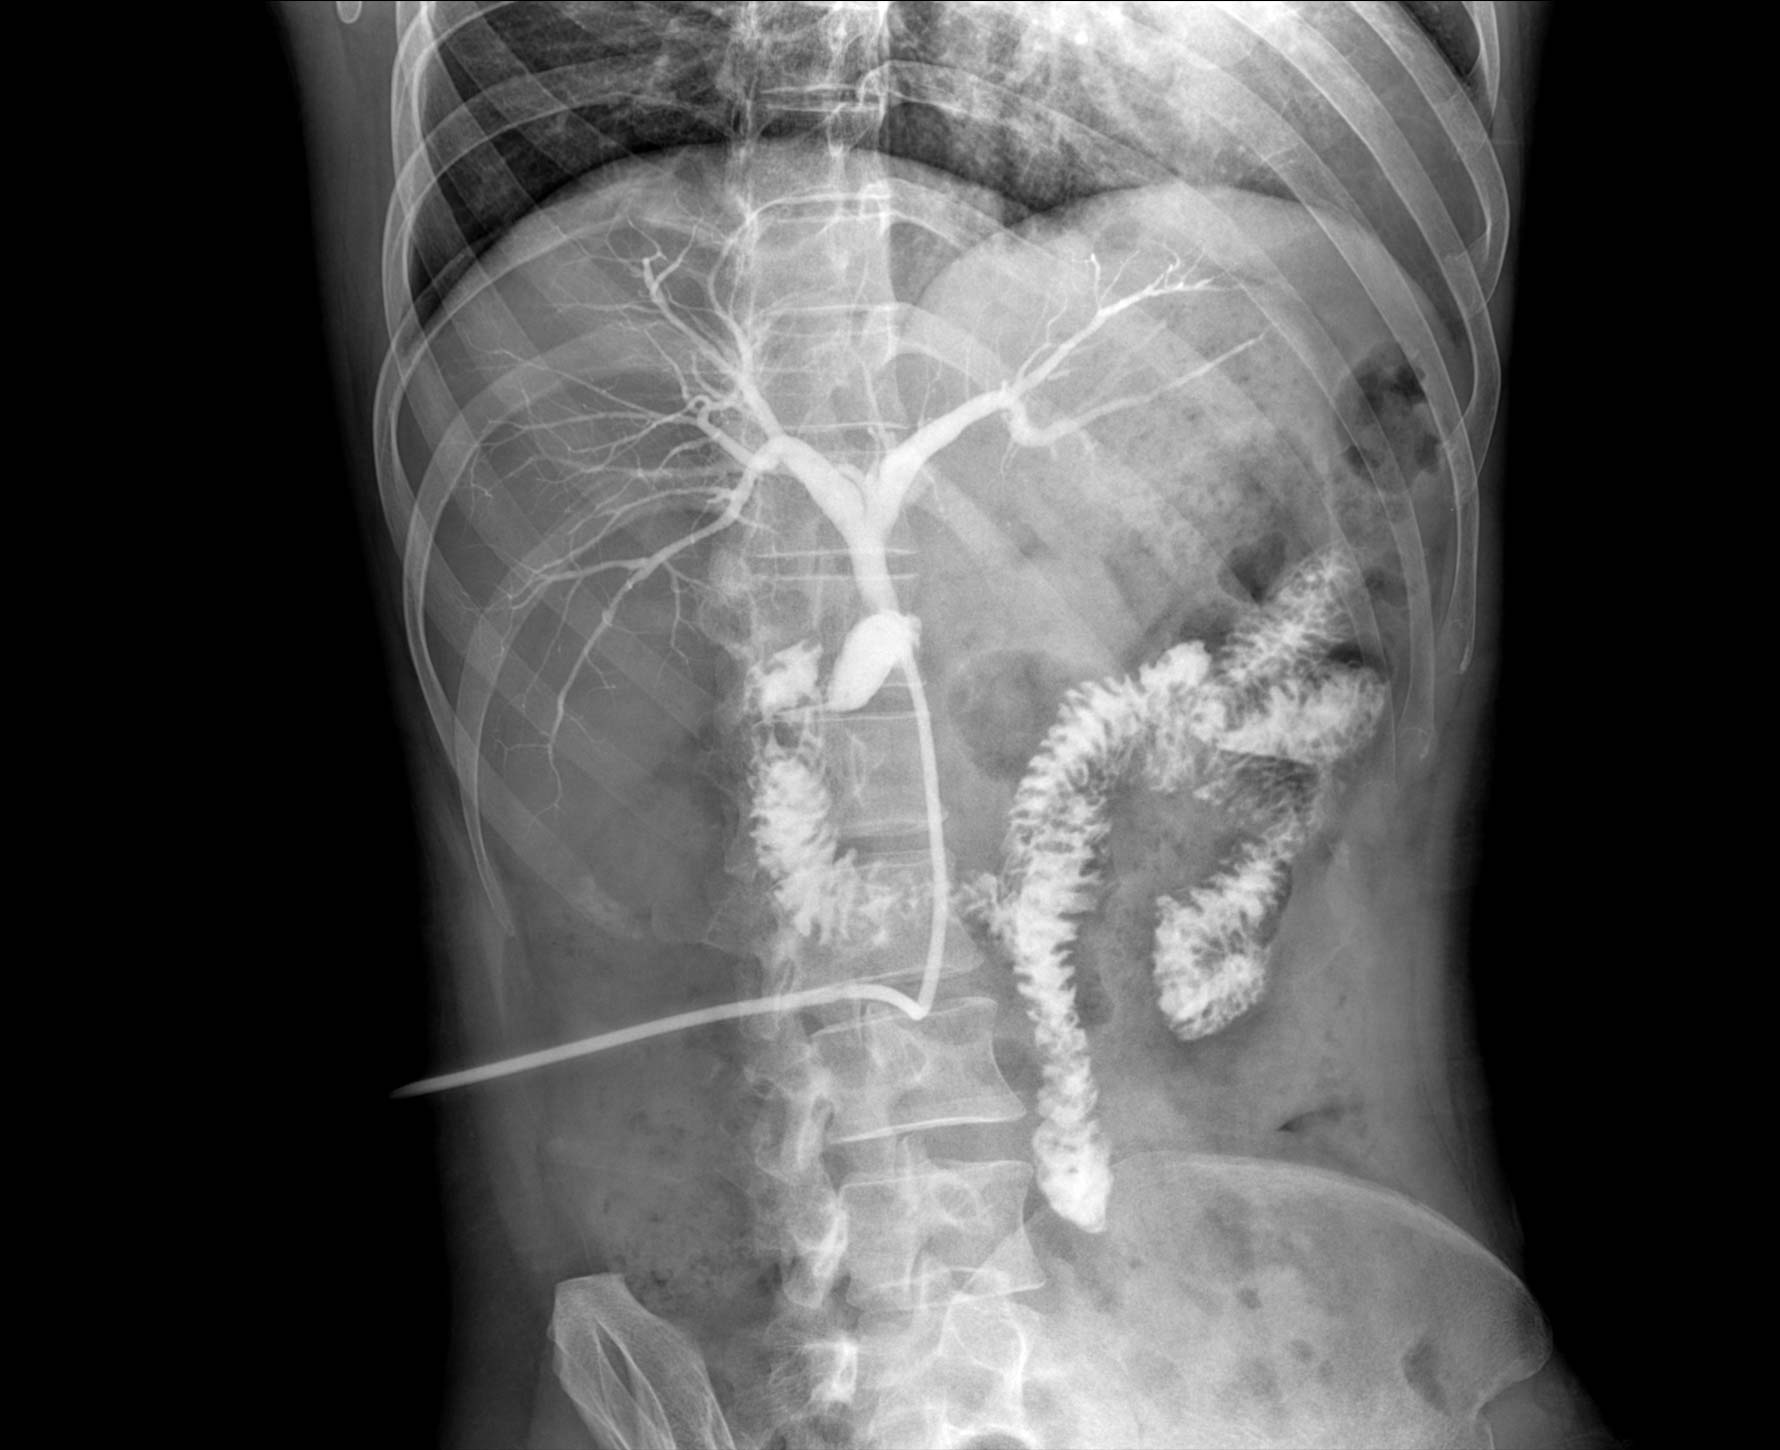

安健自主研發多項具備發明專利的圖像處理技術,成就黑科技,成就出色影像

無縫融合處理,保證高質量全景影像。